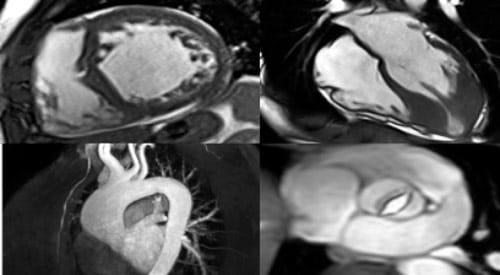

Cardiovascular Magnetic Resonance Imaging

Cardiovascular MRI is a noninvasive test used to help diagnose or monitor heart and vascular disease. This scan uses powerful magnets to produce detailed pictures of the heart and surrounding blood vessels. MRI does not use ionizing radiation (x-rays). During the scan, you may receive contrast material to enhance the imaging, which helps to identify specific diseases.